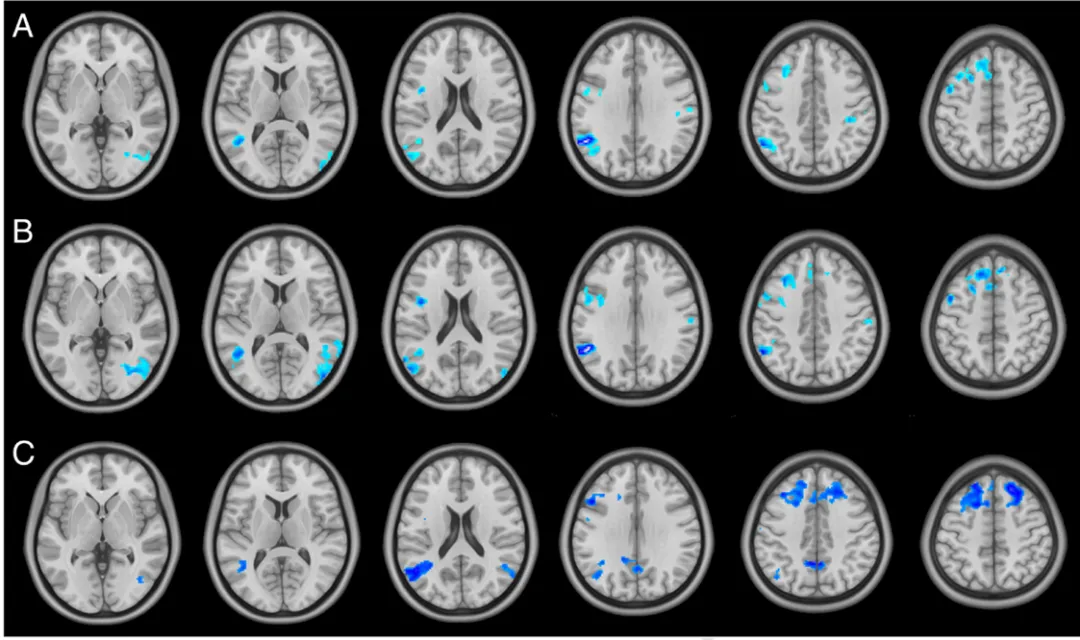

在线效应:与经颅直流电刺激(tDCS)不同,tACS 没有在刺激期间(即“在线”效应)对皮层产生显著影响。无论刺激是施加在枕叶皮层还是中央-额区,都未观察到显著的即时皮层活动变化。即时后效(aftereffect):尽管tACS在在线效应上没有表现出显著影响,但即时后效却显现出了显著的BOLD信号下降。对于施加在枕叶皮层的tACS刺激,BOLD信号下降在视觉相关区域(如下枕回和中枕回)以及一些远距离区域都得到了体现。而对于中央-额区的tACS刺激,在枕叶区域并未观察到任何显著效应。与假刺激的比较:通过将tACS在枕叶皮层的后效与假刺激的后效进行比较确认了tACS引起的BOLD信号变化的方向和空间定位:枕叶以及顶-额区域的BOLD信号出现显著下降。

图3 经颅交流电刺激(tACS)